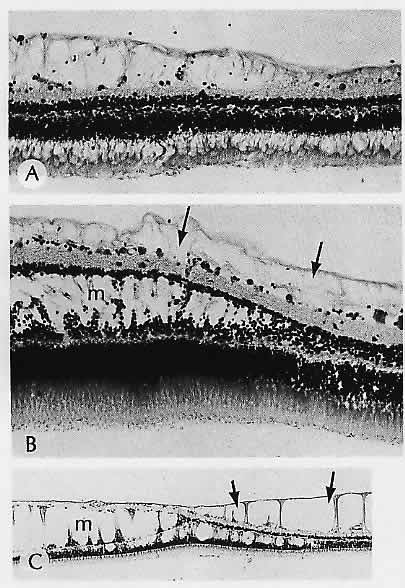

Nicholson DH (ed): Ocular Pathology Update. New York, Masson, 1980 109. Kenyon KR, Maumenee AE, Ryan SJ et al: Diffuse drusen and associated complications. Am J Ophthalmol 100:119, 1985 110. El Baba F, Green WR, Fleischmann J et al: Clinicopathologic correlation of lipidization and detachment of the retinal

pigment epithelium. Am J Ophthalmol 101:576, 1986 111. Keno DD, Green WR: Retinal pigment epithelial window defect, Arch Ophthalmol 96:854, 1978 112. Henkind P, Gartner S: The relationship between retinal pigment epithelium and the choriocapillaris. Trans Ophthalmol Soc UK 103:444, 1983 113. Yeo JH, Marcus S, Murphy RP: Retinal pigment epithelial tears: Patterns

and prognosis, Ophthalmology 95;8, 1988 114. Heriot WJ, Henkind P, Bellhorn RW: Choroidal neovascularization can digest Bruch's membrane: A prior

break is not essential. Ophthalmology 91:1603, 1984 115. Green WR, Gass JDM: Senile disciform degeneration of the macula: Retinal